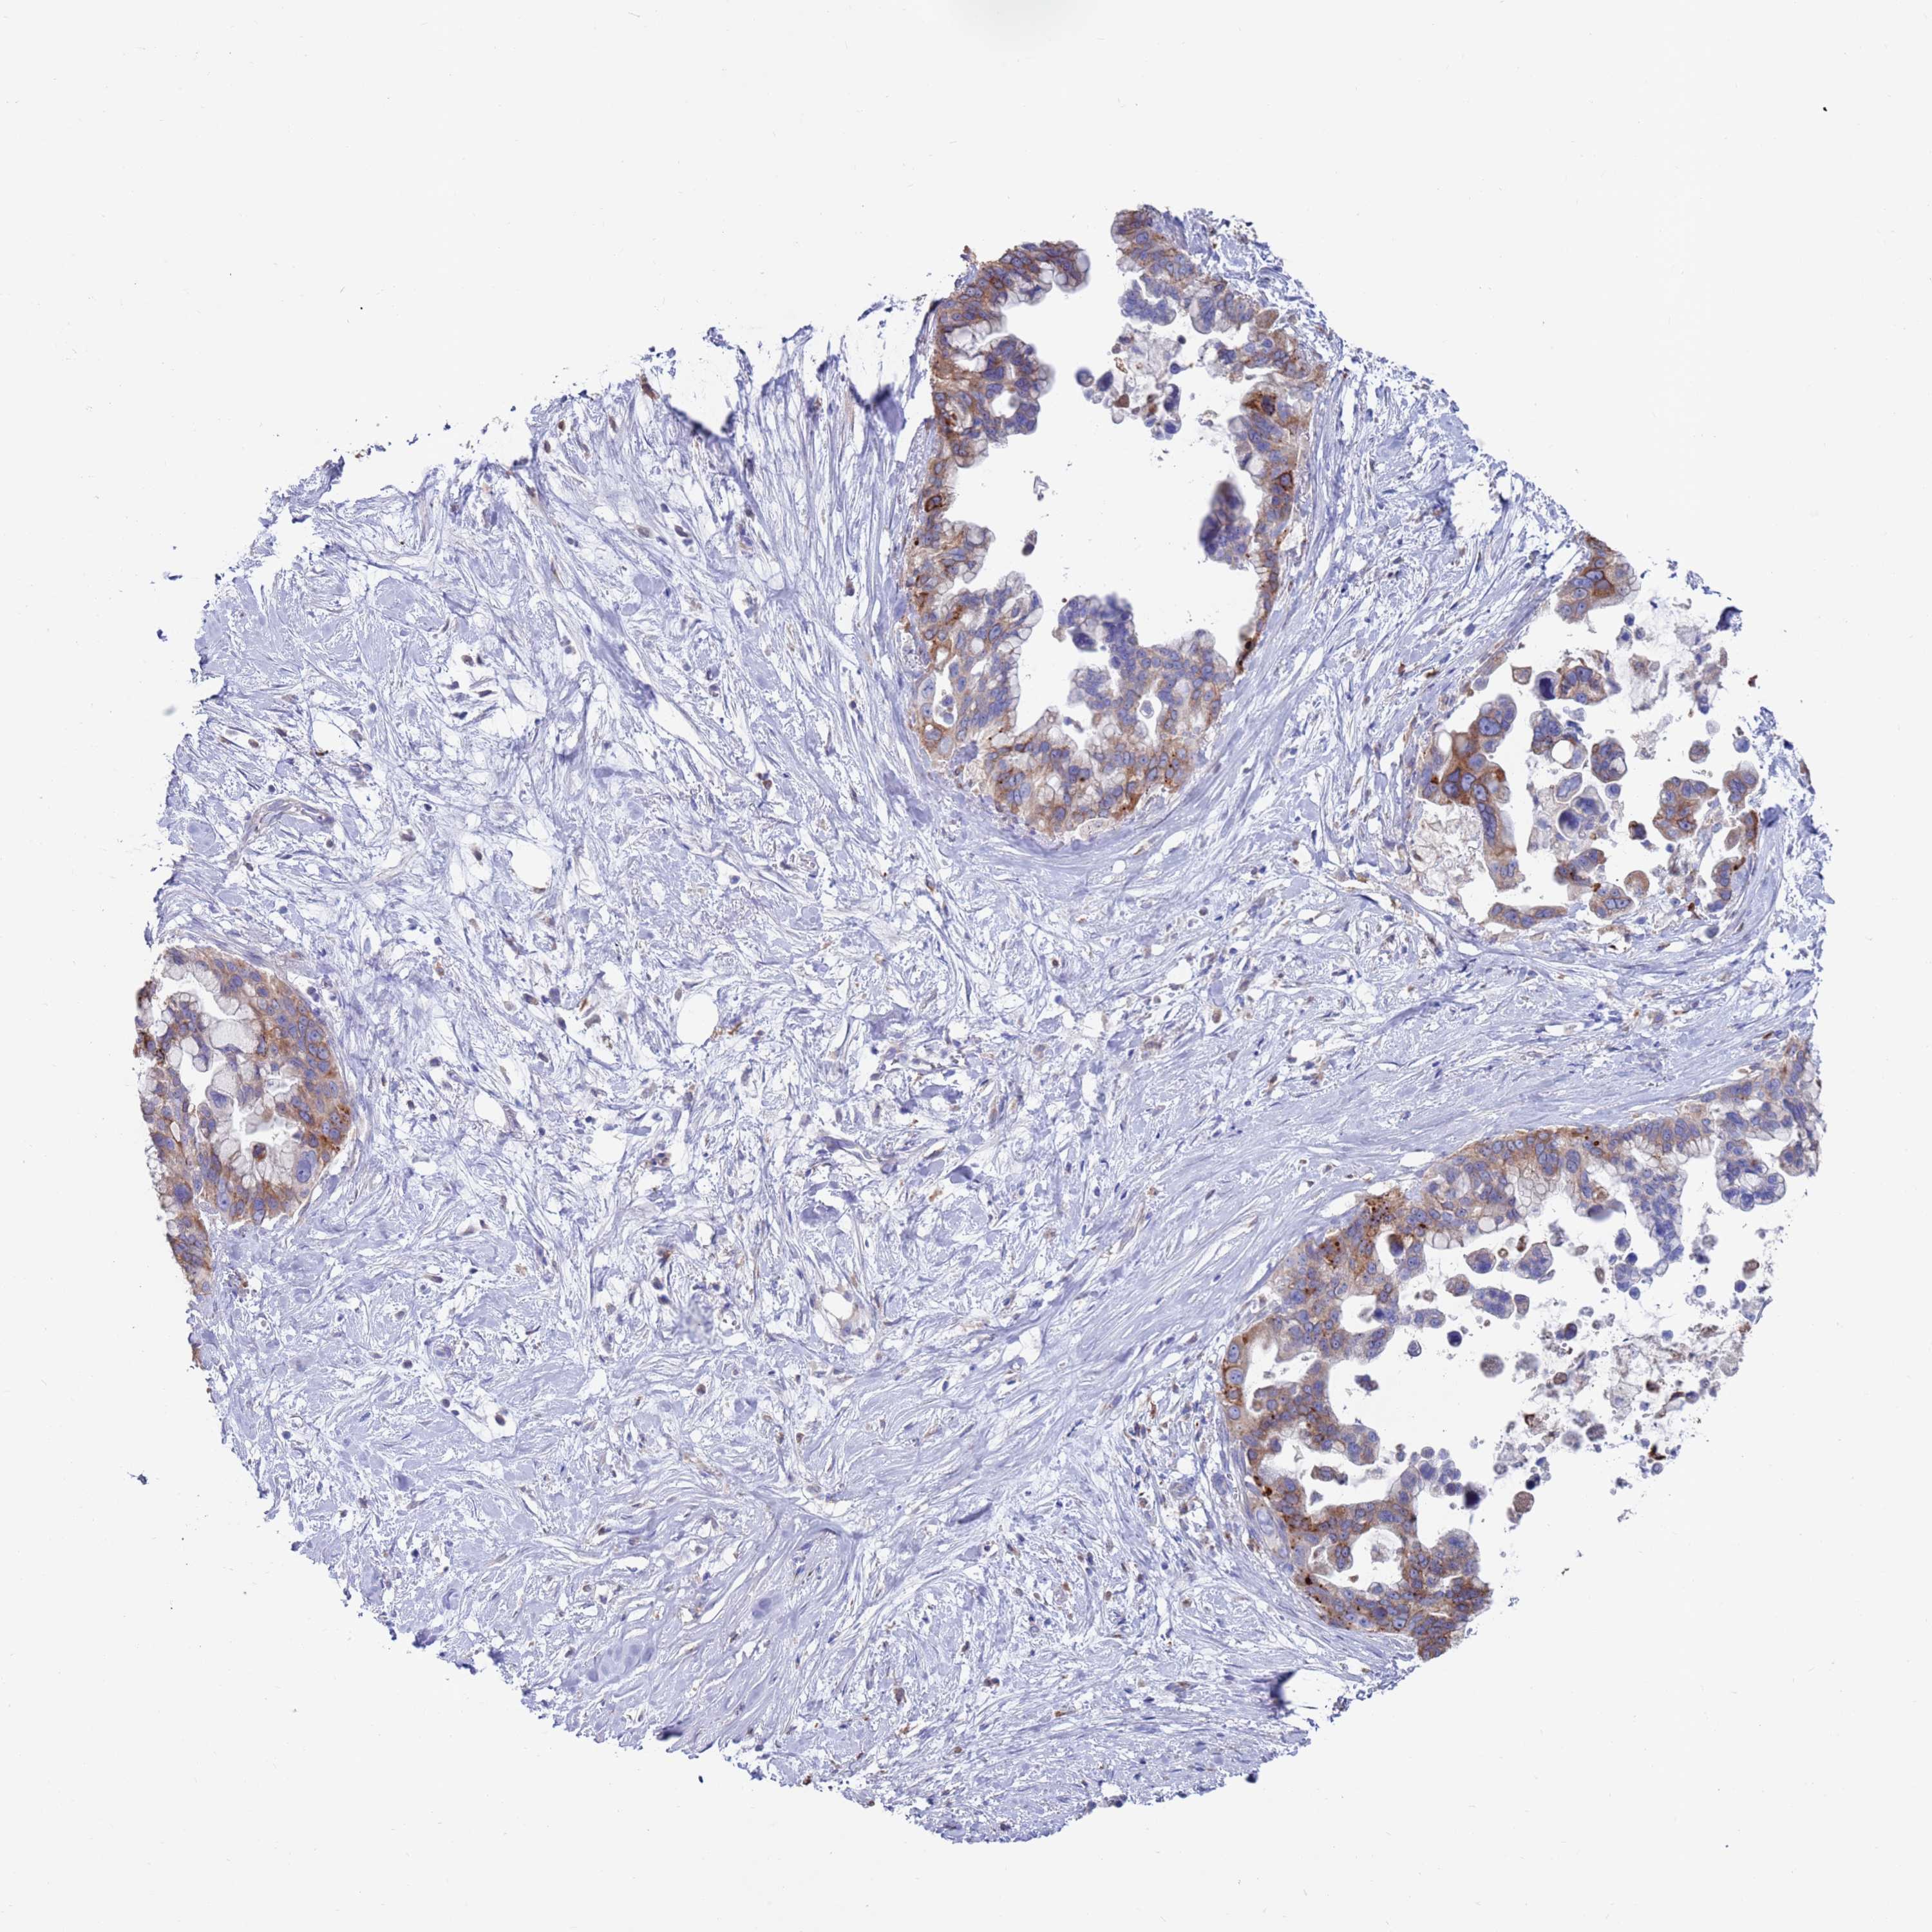

PANCREATIC CANCER - Protein expressioni

A mouse-over function shows sample information and annotation data. Click on an image to view it in a full screen mode. Samples can be filtered based on level of antibody staining by selecting one or several of the following categories: high, medium, low and not detected. The assay and annotation is described here.

Note that samples used for immunohistochemistry by the Human Protein Atlas do not correspond to samples in the TCGA dataset.

Antibody stainingi

Antibody staining in the annotated cell types in the current human tissue is reported as not detected, low, medium, or high, based on conventional immunohistochemistry profiling in selected tissues. This score is based on the combination of the staining intensity and fraction of stained cells.

Each image is clickable and will lead to virtual microscopy that enables deeper exploration of all samples and also displays staining intensity scores, fraction scores and subcellular localization as well as patient and tissue information for each sample.

Antibody HPA041647

Antibody HPA044218

Adenocarcinoma, NOS